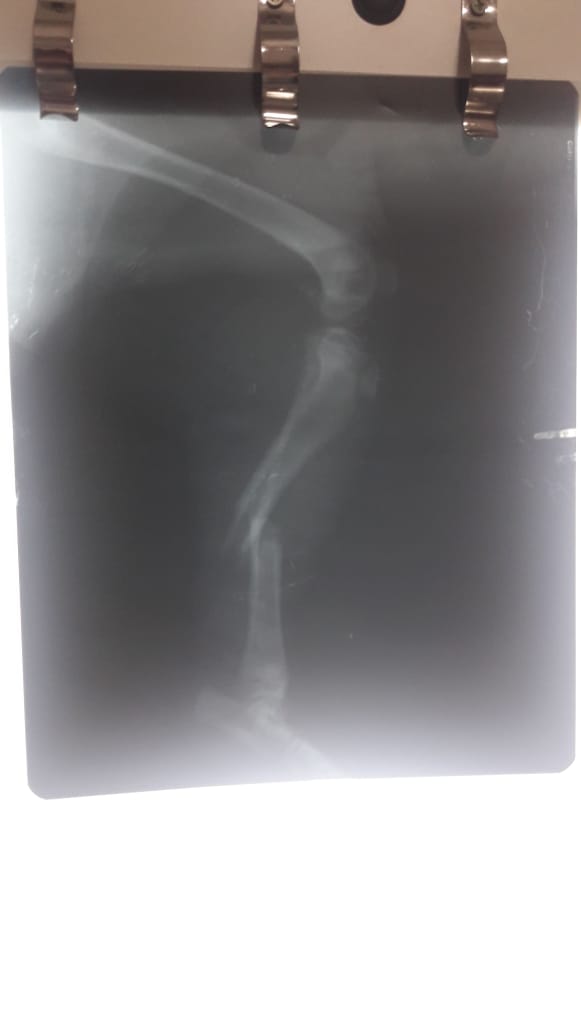

Uno de los miembros del grupo no dudó en socorrerlo y una vez que lo encontró, lo llevó a la Veterinaria El Corralito para que lo atendieran. Se le realizaron placas radiográficas que arrojaron como resultado que Tito -así se bautizó al cachorro- tenía fractura de tibia y peroné. Luego se lo intervino quirúrgicamente para reconstituir las fracturas.